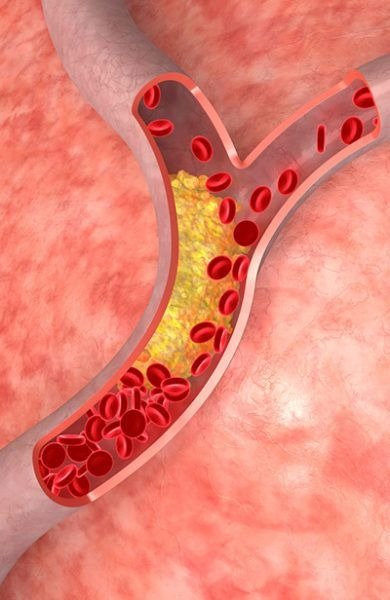

Kidney transplant is one of the most commonly performed procedures in India. It is recommended for patients with chronic kidney disease or kidney failure who are dependent on dialysis.

Liver transplant is performed for patients suffering from liver cirrhosis, liver failure, or liver cancer. India offers advanced surgical techniques with high success rates.